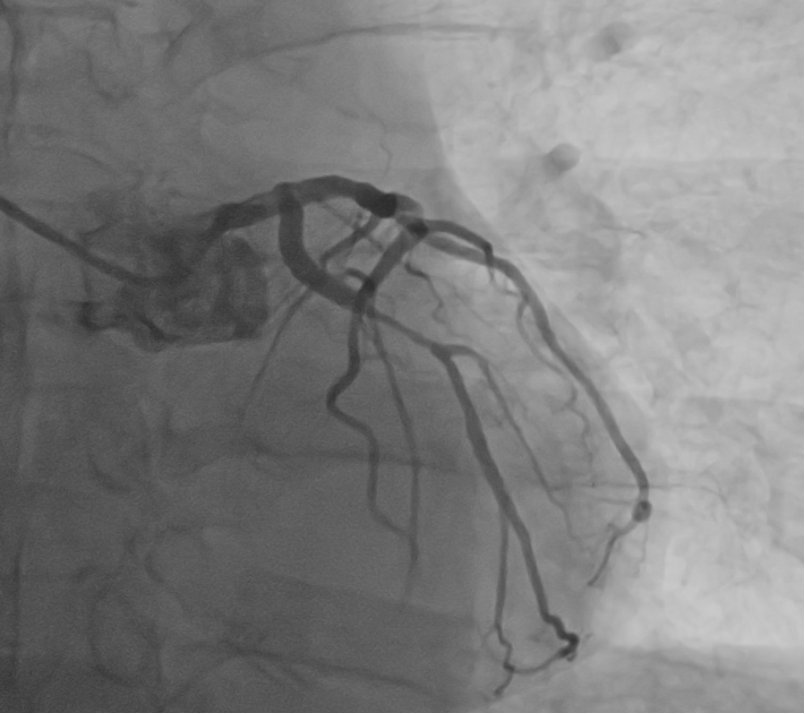

术前冠脉造影,回旋支重度狭窄

术后冠脉造影,回旋支支架术后未见狭窄患者是一名65岁男性,入院诊断冠心病,不稳定型心绞痛,经术前冠脉CTA评估提示回旋支重度狭窄,进一步行冠脉造影及介入治疗。2月4日,患者完成冠脉造影,结果示双支病变,回旋支重度狭窄,前降支中度狭窄,结果同术前冠脉CTA。经心内科主任医师姚道阔、副主任医师何晓全与主治医师化冰共同讨论,认为该患者符合冠脉介入手术指征,并且符合血管介入控制系统辅助完成冠脉介入手术入组条件,团队决定在血管介入手术控制系统辅助下完成冠脉介入手术。